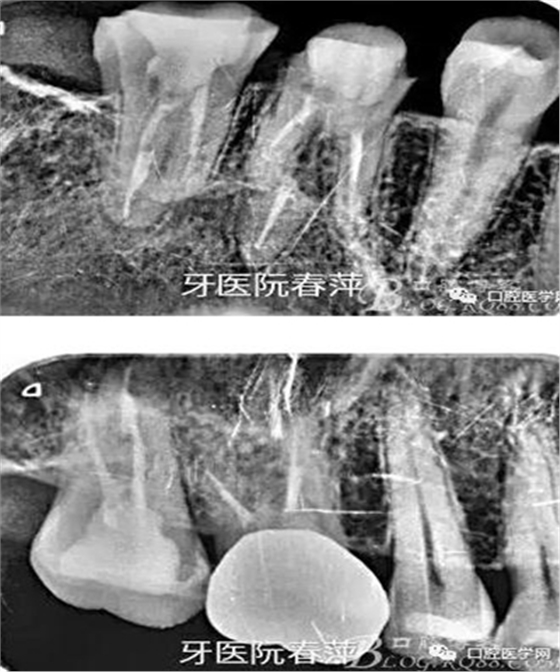

第一步,去除27的銀汞充填材料,發(fā)現(xiàn)髓腔破壞大,繼發(fā)齲明顯,牙體變色。

27的治療過程不太順利,主要是干髓近10年,根管很難疏通。腭根最先預備,比較粗大。近頰根不通暢,選中頰根找不到。

絢彩AT無飾瓷全形態(tài)氧化鋯產品體驗+全冠和嵌體微創(chuàng)修復后牙

因為缺乏顯微鏡的幫助,27的根管預備花了很長時間,最后終于找到3個根管也基本疏通到位。完善的根管治療是修復的根本,這個是什么時候都不能改變的基礎觀念。